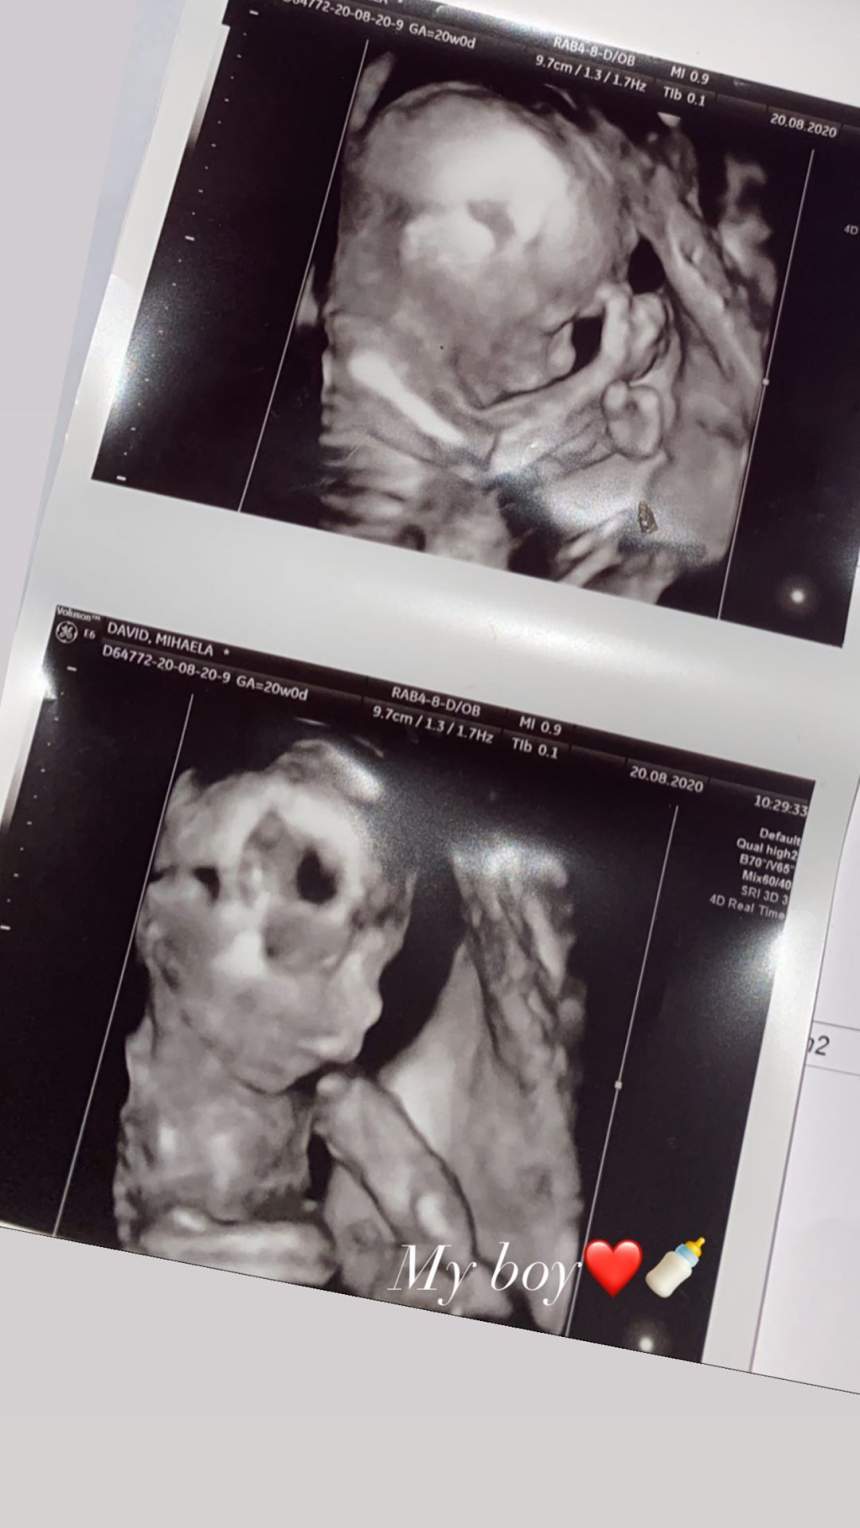

Fiul lui Florin Salam este în culmea fericirii! La numai 18 ani, Dani Stoian va deveni tătic și nu-și mai încape în piele de mândrie. În plus, tânărul nu s-a putut abține și, recent, a postat pe contul de Instagram prima fotografie cu cel mic, mai exact, ecografia băiețelului său. Ipostaza emoționantă desigur că a venit însoțită de un mesaj pe măsură!

Fiul lui Florin Salam a postat ecografia băiețelului său